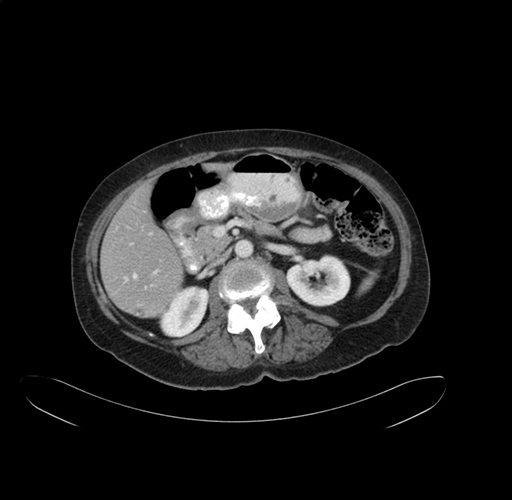

Axial Venous